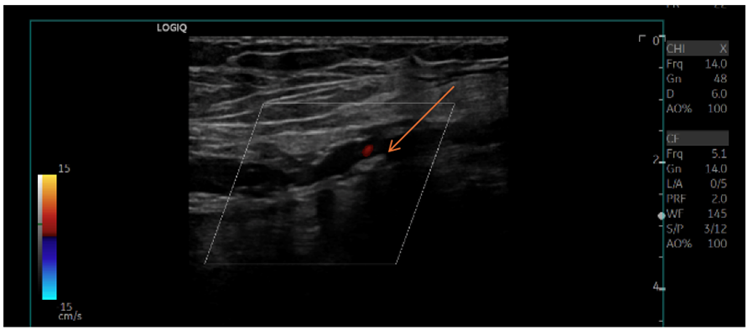

Five-days after initiation of the therapeutic regimen, the patient developed symptoms suggestive of arterial embolization of the right lower extremity. Further evaluation confirmed ischemia (Rutheford IIa) due to thrombosis of the right common femoral artery (Figure 5). However, the patient declined surgery given the significant perioperative risk.

Figure 5: Doppler ultrasound of right lower extremity revealing the presence of thrombus in the right common femoral artery (arrow).